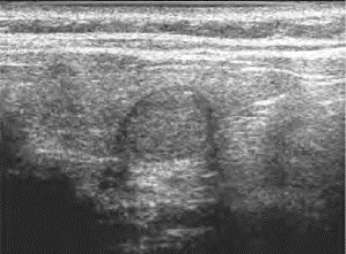

图7-7 甲状腺腺瘤声像图

甲状腺右叶中下部腺瘤(纵切面),边界清晰,类圆形,有声晕

腺体内见实性包块,单发多见,边界清楚,呈椭圆形或圆形,有包膜及低回声晕环,其余甲状腺组织回声正常。瘤体内部回声基本均匀,呈中等或偏低回声,后回声可增强或正常。较大的腺瘤内部可伴有坏死液化,呈囊实性回声。部分腺瘤内部可出现钙化灶,但比较粗大,另外可见结晶体的出现(图7-7)。